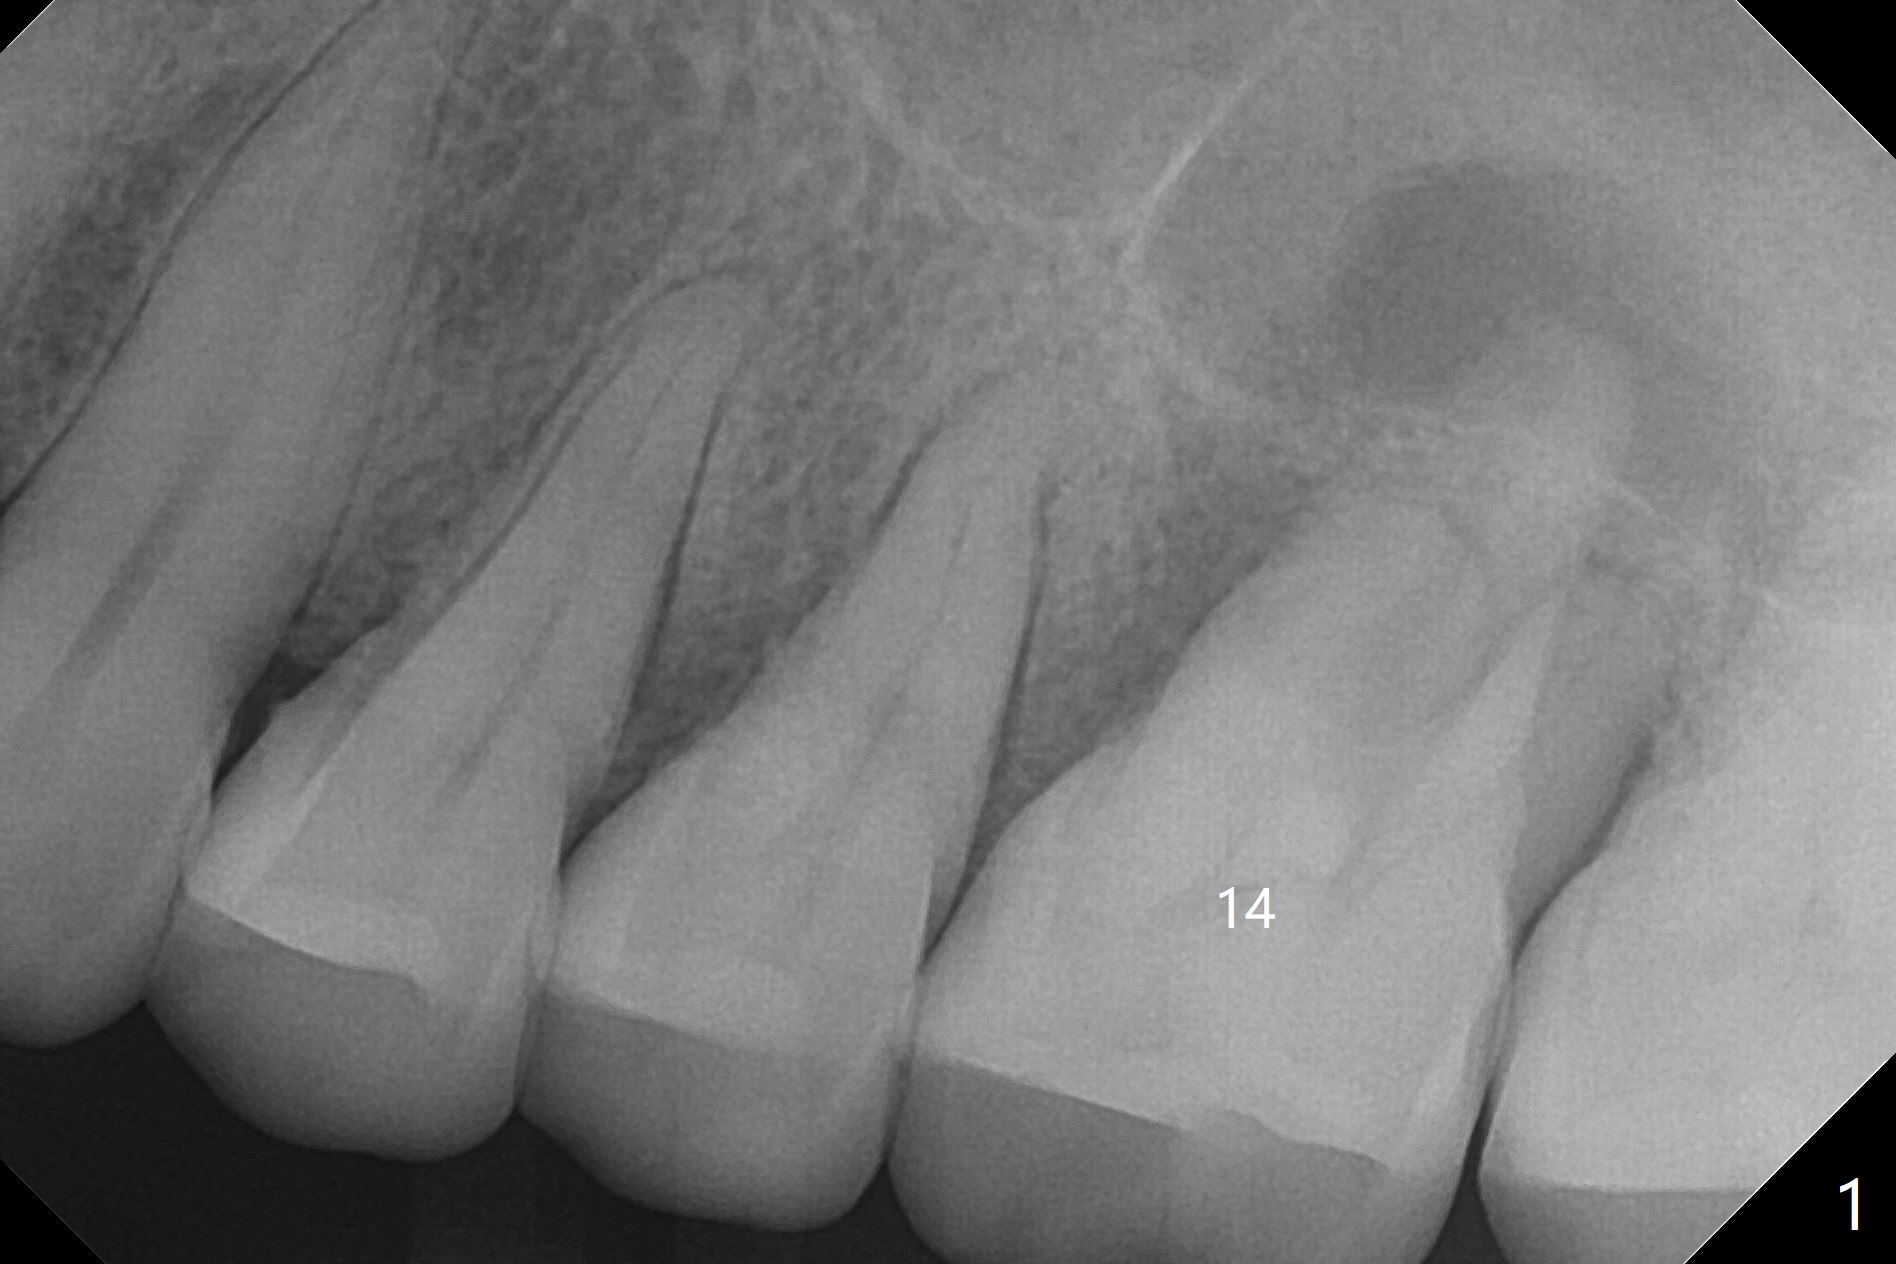

A 51-year-old woman with chronic periodontitis has difficulty masticating on the left side. The tooth #14 (Fig.1) has severe palatal gingival recession (Fig.2), apparently without palatal plate. CT will be taken prior to treatment. After extraction, PRF plug will be inserted to the palatal socket, while bone graft will be placed in the buccal ones. Two PRF membranes will be used for socket opening coverage. CT will be taken postop. The case will test whether PRF will regenerate bone by taking 4 months postop.

血小板纤维素膜(PRF)制作方法各式各样,今晚探讨的是L-PRF(L: 白细胞),作者认为L-PRF能促进骨再生,一般观点PRF只利于软组织愈合。51岁女,左上第一磨牙严重牙周炎(图一: 14),腭侧根暴露 (图二),拔除后,腭侧牙槽窝放置PRF,而颊侧牙槽窝放置骨粉,估计骨粉放在腭侧窝,可能不容易固定。万一自我发明PRF不能促进骨形成,植体能植入颊侧牙槽窝。术前术后(即刻,四个月)拍摄局部CT。